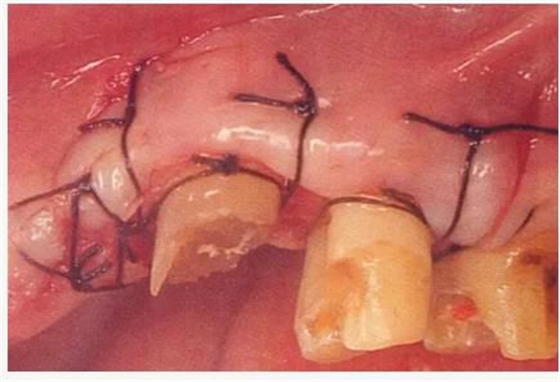

病例3 對(duì)于上頜前牙部的齦下齲壞,通過(guò)APF和FGG進(jìn)行治療的病例

圖6-1

上頜前牙的牙頸部及齦下存在齲壞。

圖6-2 初診時(shí)的X光照片。齦下齲壞延伸到牙槽嵴頂,根管治療也不徹底。